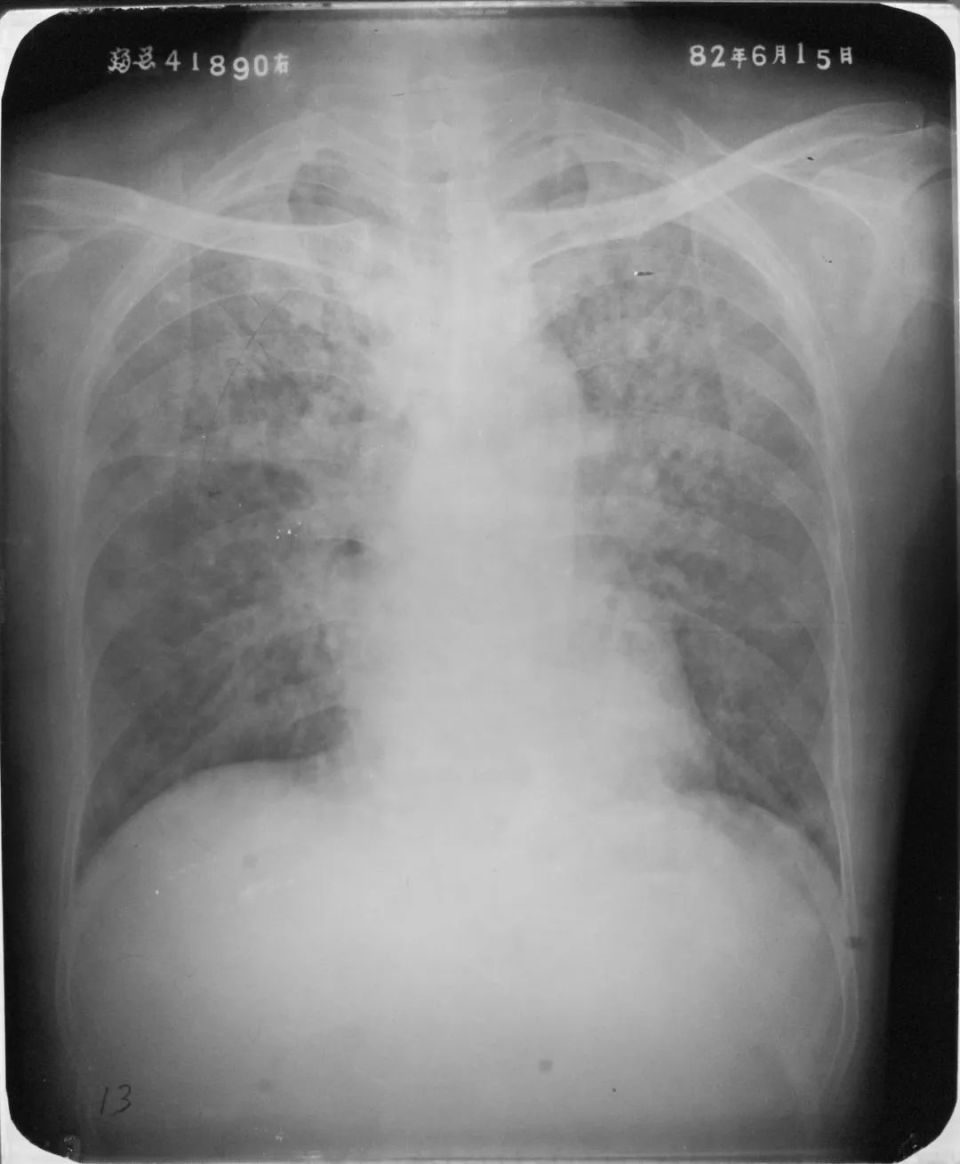

双肺化脓性肺炎

图片

胸部正位片示:两肺多发小片状密度增高影,边缘模糊。另见大小不等的圆形或椭圆形结节状阴影,边缘较清楚,部分可见空洞